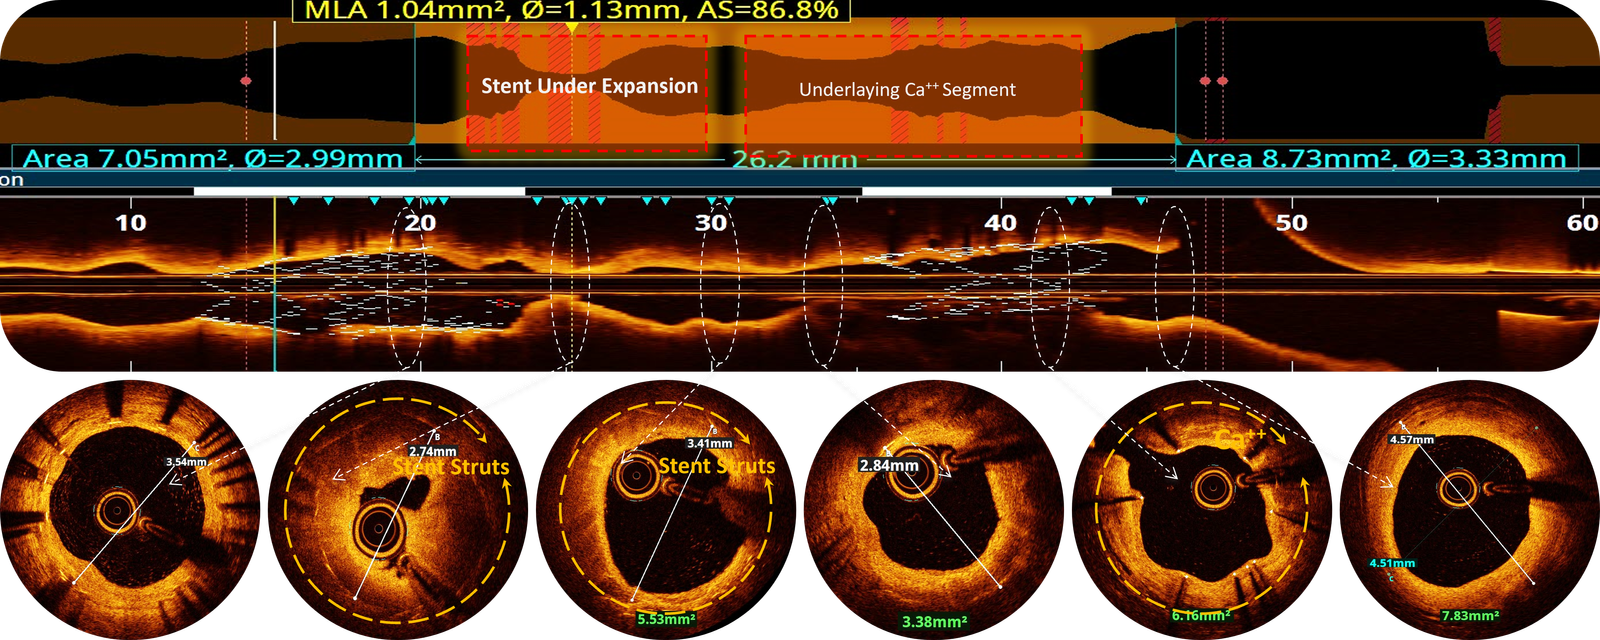

Post-IVL & high-pressure dilation OCT-run Ca++ score analysis.